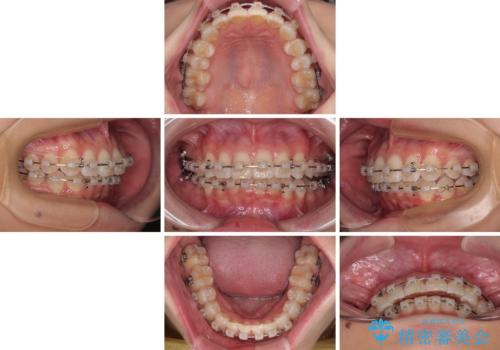

マウスピースでもワイヤーでも対応可能でしたが、煩わしいことは避けたいとのことで、舌のトレーニングをしっかりと行っていただきながら、ワイヤー装置にて矯正治療を行うこととしました。

なかなか舌の突出癖が改善できず、上下前歯が非接触となる期間が長く続きました。

アンカースクリューの活用と、舌のトレーニングを何度も指導し、出っ歯になることなく無事に治療を終えることができました。